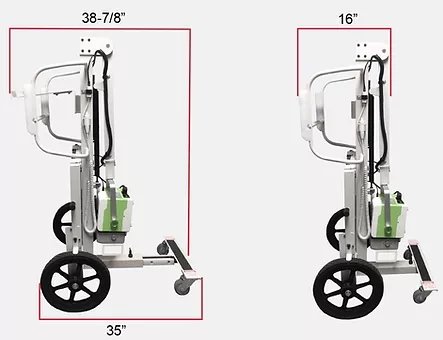

- Lightweight: 100 pounds

- Compact: 26” Wide x 53" High x 39" Deep